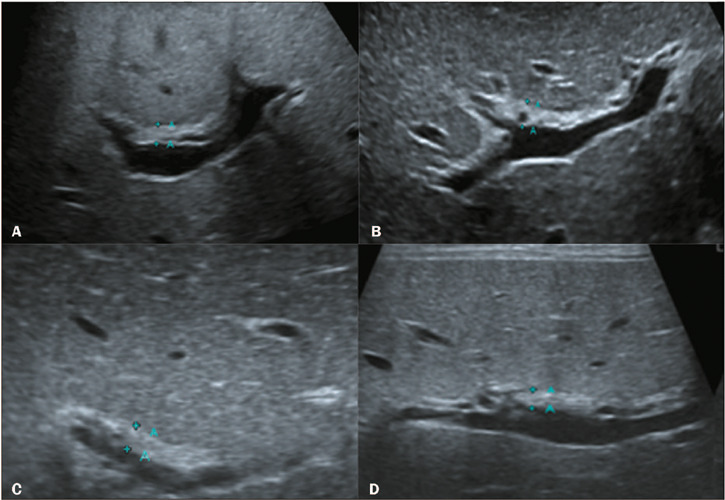

Materials and methods: This was a retrospective study of the ultrasound images of 44 patients with neonatal cholestasis. We excluded 18 patients in whom a final diagnosis of BA was not confirmed or who were lost to clinical follow-up. The main ultrasound findings evaluated were gallbladder length and morphology; triangular cord thickness; hepatic artery enlargement; hepatic subcapsular flow; cysts in the porta hepatis; presence of a distinct triangular cord with linear, tubular, or round hypoechoic portions; and polysplenia syndrome.

Results: Abnormal gallbladder morphology and triangular cord thickening were the main ultrasound findings in the patients with BA. Gallbladder abnormalities were present in all patients. Hepatic artery enlargement was the third most common finding, present in 19 (73%) patients. Six patients (23%) had subcapsular arterial flow and four (15%) had cysts in the porta hepatis. Hypoechoic or cystic portions of the triangular cord were present in three patients (11%), and we found that BA was accompanied by polysplenia syndrome in three patients (11%).